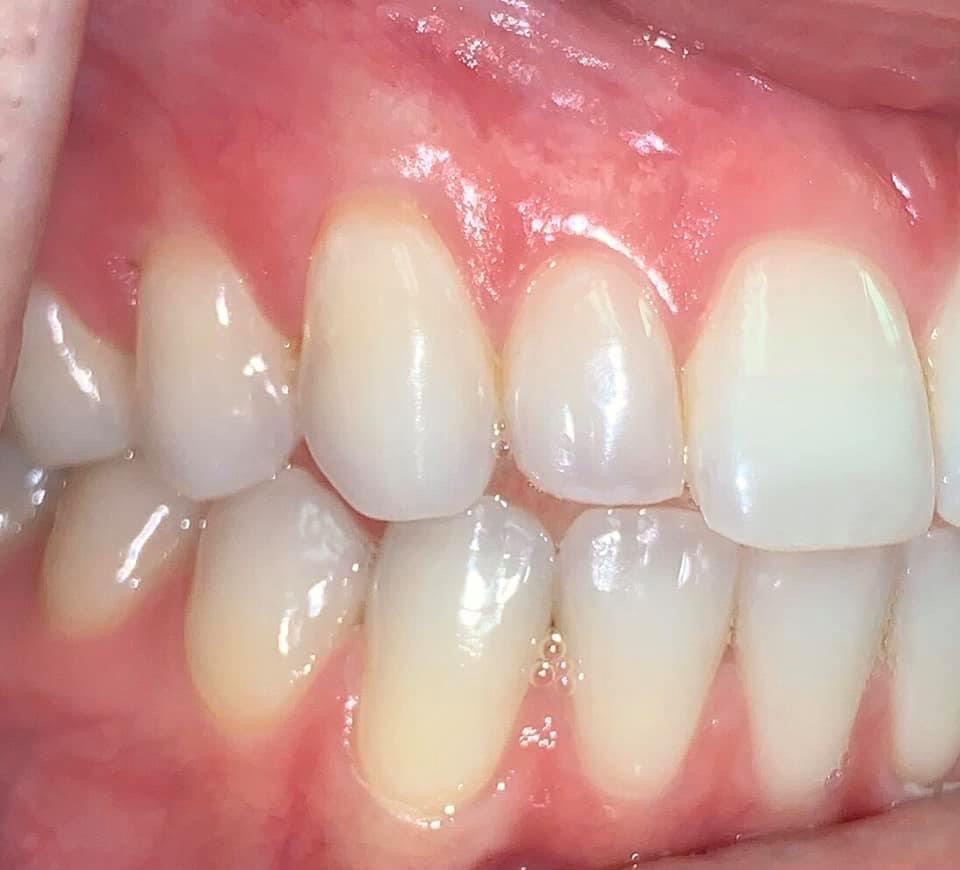

BEFORE AND AFTER PICTURES: